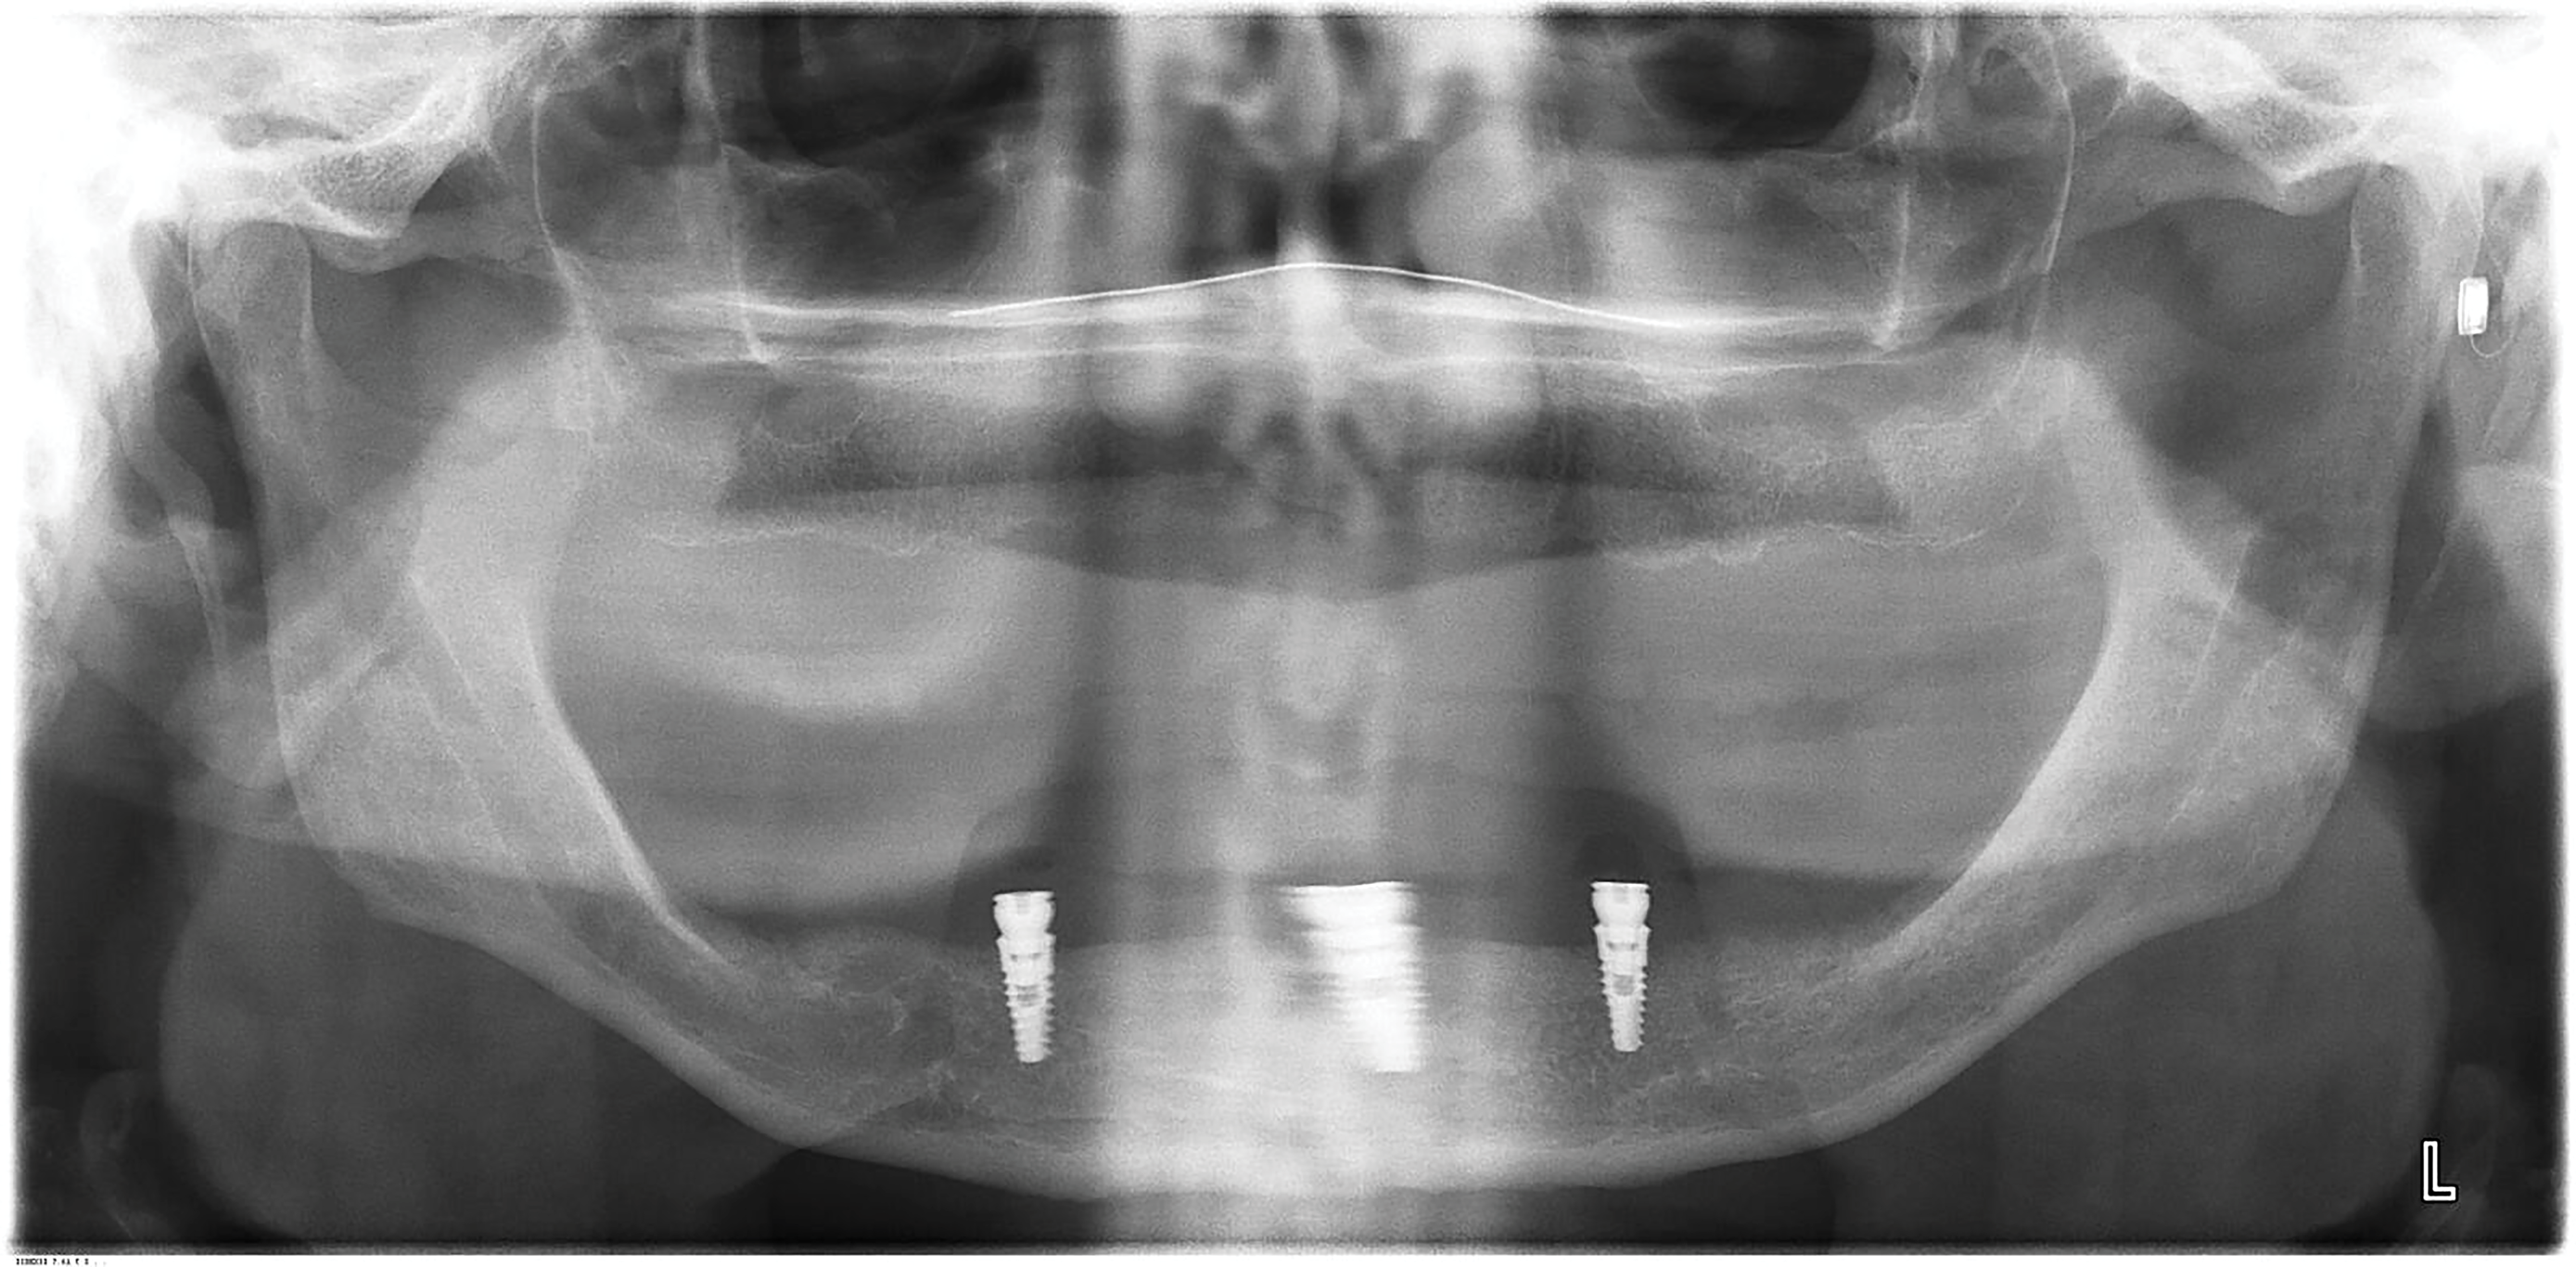

The patient's radiographic assessment, performed immediately following the initial clinical evaluation, included a panoramic radiograph (Figure 4) and bitewing and periapical radiographs of No. 30 (Figure 5). Panoramic findings showed generalized horizontal bone loss confined to the coronal third (15% to 20%), with circumferential bone loss, also referred to as "cupping," around both of the patient's implants, Nos. 30 and 13.

Fig 4. Panoramic radiograph. Both implants (Nos. 13 and 30) demonstrated similar horizontal bone loss confined to the coronal one-third.

Figure 4